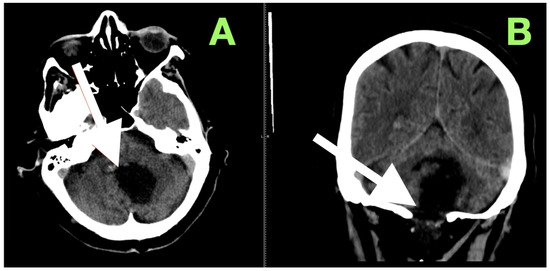

Background and Clinical Significance: Fourth ventricular epidermoid cysts are among the least frequently encountered intracranial tumors (less than 1%). Their slow growth pattern along cisternal and subarachnoid spaces, and their close proximity to neurovascular structures (brainstem–cerebellar), create difficulty for surgical treatment. Total [...] Read more.

Background and Clinical Significance: Fourth ventricular epidermoid cysts are among the least frequently encountered intracranial tumors (less than 1%). Their slow growth pattern along cisternal and subarachnoid spaces, and their close proximity to neurovascular structures (brainstem–cerebellar), create difficulty for surgical treatment. Total removal is often complicated by the capsule’s adherence to eloquent structures and requires a thoughtful surgical approach of weighing radical resection versus neurologic/function preservation. This case description provides an example of using careful clinical–radiological correlation and anatomy-dissecting microsurgery as a method of permanent decompression and neurologic recovery with low operative risk. Case Presentation: A 57-year-old female presented with impaired stability of gait, gaze-evoked nystagmus, appendicular ataxia, minimal ipsilateral hypotonia, and mild bulbar dyscoordination. Imaging (MRI, MRA) revealed a large, lobulated mass that was lobulated and avascular centered in the left cerebellar hemisphere, with an extension into the vermis and cisterna magna, and partial filling of the fourth ventricle with classic epidermoid imaging. Resection was performed via a midline suboccipital telovelar approach with microsurgery, relying on native arachnoid planes and quadrant opportunities of decompression, while preserving critical neurovascular structures. A thin rim of capsule intimately adherent to the floor of the ventricle was intentionally left to minimize irreversible cranial nerve injury. Histology showed keratinizing stratified squamous epithelium with laminated keratin and cholesterol clefts. Following resection, truncal stability, limb coordination, and ocular pursuit improved without additional deficits. Initial and 3-month postoperative MRI showed total decompression, re-established CSF pathways, and no recurrence. Conclusions: This case demonstrates that maximal safe resection (with function preservation) through natural anatomy corridors can achieve excellent neurologic results in fourth ventricular epidermoids. Lifelong MRI surveillance will be needed due to the srisk of delayed recurrence even after near-total resection. Full article